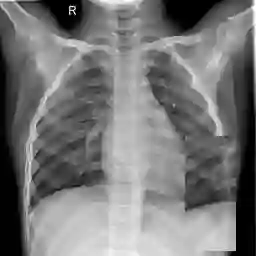

Large numbers of labeled medical images are essential for the accurate detection of anomalies, but manual annotation is labor-intensive and time-consuming. Self-supervised learning (SSL) is a training method to learn data-specific features without manual annotation. Several SSL-based models have been employed in medical image anomaly detection. These SSL methods effectively learn representations in several field-specific images, such as natural and industrial product images. However, owing to the requirement of medical expertise, typical SSL-based models are inefficient in medical image anomaly detection. We present an SSL-based model that enables anatomical structure-based unsupervised anomaly detection (UAD). The model employs the anatomy-aware pasting (AnatPaste) augmentation tool. AnatPaste employs a threshold-based lung segmentation pretext task to create anomalies in normal chest radiographs, which are used for model pretraining. These anomalies are similar to real anomalies and help the model recognize them. We evaluate our model on three opensource chest radiograph datasets. Our model exhibit area under curves (AUC) of 92.1%, 78.7%, and 81.9%, which are the highest among existing UAD models. This is the first SSL model to employ anatomical information as a pretext task. AnatPaste can be applied in various deep learning models and downstream tasks. It can be employed for other modalities by fixing appropriate segmentation. Our code is publicly available at: https://github.com/jun-sato/AnatPaste.